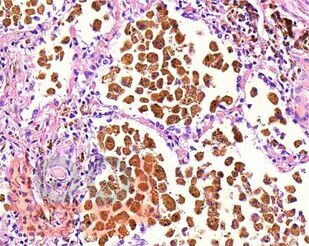

В атласе представлены авторские снимки макро- и микропрепаратов, демонстрирующих типовые проявления патологических процессов. В цветных иллюстрациях в описании макро- и микропрепаратов сделан акцент на наиболее важных макроскопических и гистологических изменениях, позволяющих диагностировать и дифференцировать состояния, отклоняющиеся от нормы, в том числе с использованием различных гистологических окрасок. Атлас помогает выделить главные аспекты изучаемых патологических процессов, организовать и конкретизировать учебный процесс.